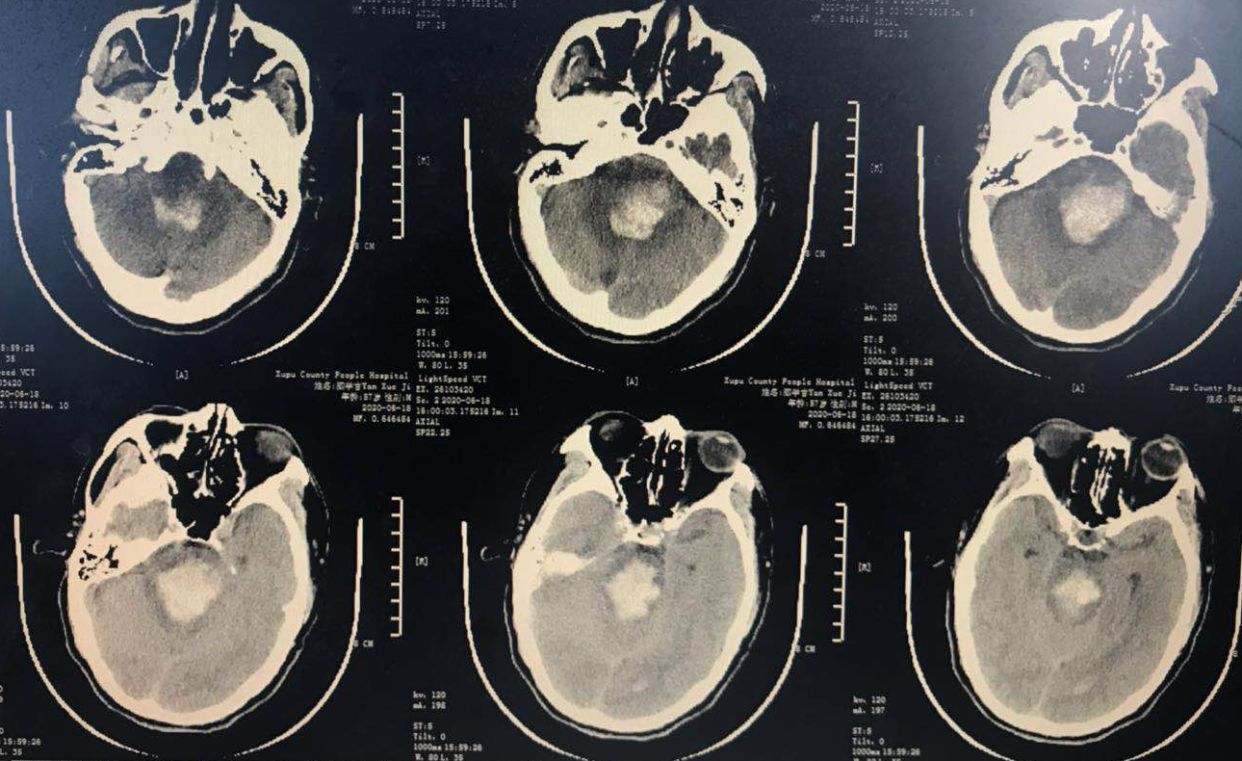

术前CT,桥脑出血。

术前动态CT